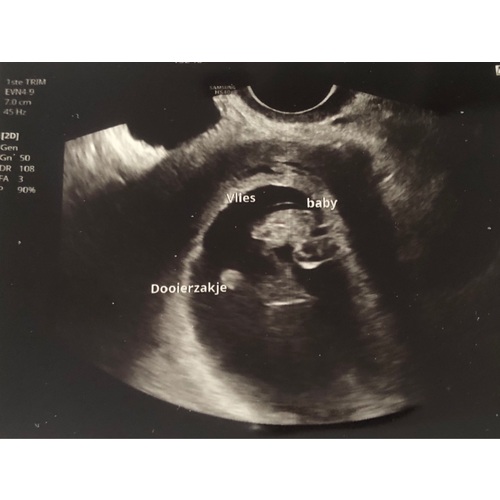

Ik heb er twee gehad in dezelfde week. Eentje was een 3d echo en eentje een 2d bij de gynaecoloog. Ik vond dit buiten beetje oncomfortabel na een tijdje geen probleem. Vooral met de 3d echo lag ik er echt een halfuur. De echo's waren gemaakt met 8 weken.